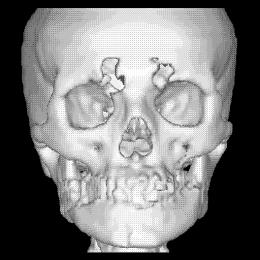

La figura 1‑9 mostra un esempio di surface rendering. Si noti come grazie all’ombreggiatura si avverte la sensazione di tridimensionalità.

Figura 1‑9 Ricostruzione 3D in surface rendering